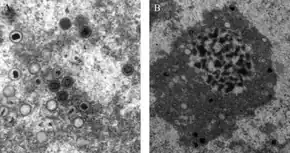

| CMV infection of a human lung pneumocyte | |

CMV infection can be demonstrated microscopically by the detection of intranuclear inclusion bodies. On H&E staining, the inclusion bodies stain dark pink and are called "owl's eye" inclusion bodies.[51]HCMV infection is important to certain high-risk groups.[52] Major areas of risk of infection include pre-natal or postnatal infants and immunocompromised individuals, such as organ transplant recipients, or those infected with human immunodeficiency virus (HIV). In HIV infected persons, HCMV is considered an AIDS-defining infection, indicating that the T-cell count has dropped to low levels.Lytically replicating viruses disrupt the cytoskeleton, causing massive cell enlargement, which is the source of the virus' name.[48][16][1]